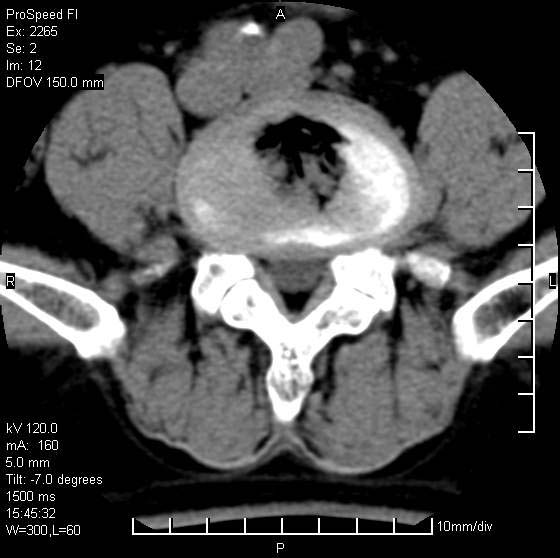

以下是引用qiushi在2007-8-22 17:26:00的发言:[br]没骨窗![br] 1、 l5~s1间盘膨出伴轻度突出(中央型)、变性。[br] 2、l4~5间盘膨出伴突出(右侧远外侧型)。[br] 3、l3~4间盘膨出。[br] 4、腰椎退行性变。[br]

以下是引用随缘的人在2007-8-22 20:56:00的发言:[br]腰椎退行性变:1。l4/5,l5/s1膨出[br] 2。l5/s1间盘退行性变 [br] 3。腰椎骨质增生

以下是引用liaizhi在2007-8-22 22:13:00的发言:[br]1,l4-5锥间盘膨出,2,l5-s1椎间盘膨出并退变(椎间盘呈真空征);3,血管瘤(椎体骨小梁稀疏粗大)?